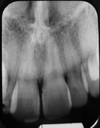

2

Q

A

Intermaxillary suture RL

3

Q

What foramen

A

Incisive foramen RL

4

Q

3 structures

A

Nasal Fossa RL and Nasal fossa walls RP

Nasopalatine Canals RL